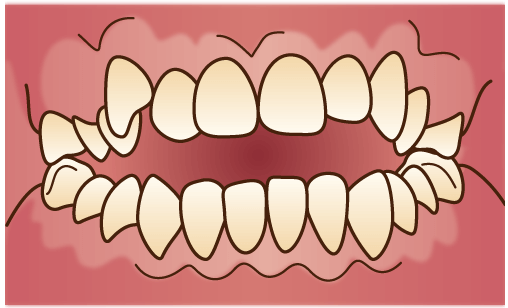

叢生(そうせい)

代表的なものが「八重歯」です。歯がでこぼことズレていたり、重なって生えている状態です。顎が小さいために歯が並ぶスペースが足りない場合や、顎に対して歯が大きすぎる場合に起こりやすくなります。

代表的なものが「八重歯」です。歯がでこぼことズレていたり、重なって生えている状態です。顎が小さいために歯が並ぶスペースが足りない場合や、顎に対して歯が大きすぎる場合に起こりやすくなります。